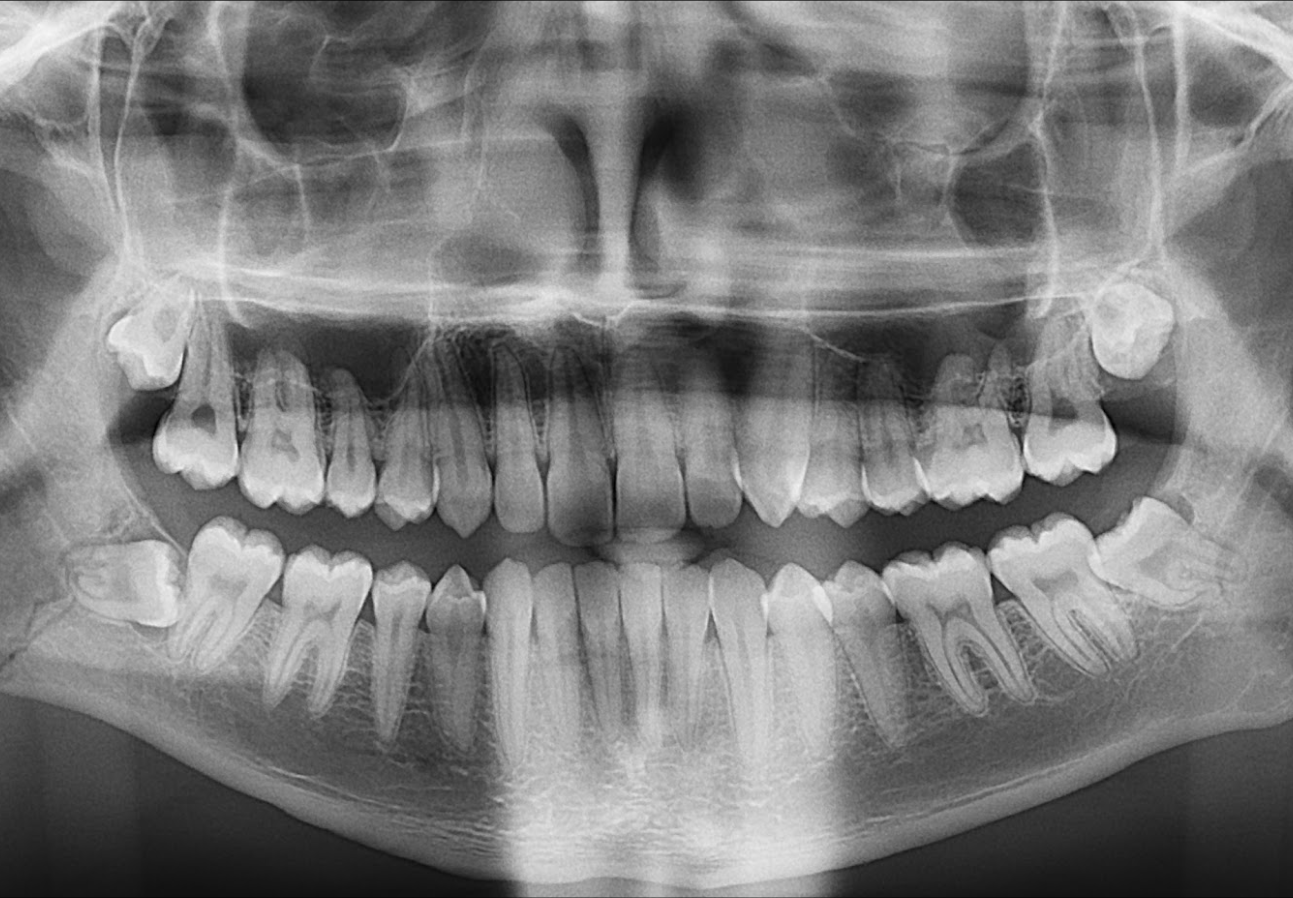

En la radiografía panorámica (Figura 1), se evidencia linea radiolucida que se extiende desde cima de reborde alveolar a nivel de zona retromolar hasta zona anterior del angulo mandibular.

Radiografia Panorámica